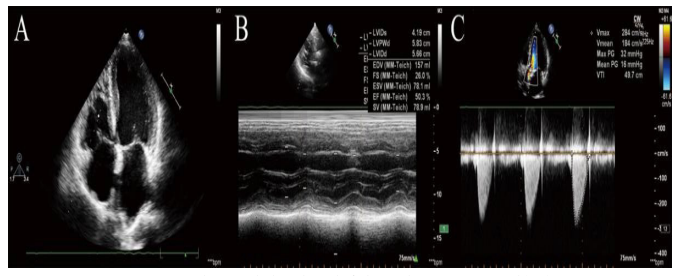

A 74-year-old male patient presented to the emergency department with progressive shortness of breath for several months. He also reported a harsh cough with occasional purulent sputum production. He had a history of AS, hypertension and coronary arterydisease. His AS and coronary artery disease were treated with conservative treatment. Physical examination revealed a 5/6 systolic murmur in aortic area and bilateral lower extremity edema. Transthoracic echocardiography (TTE) and Transesophagealechocardiogram (TEE) demonstrated an extremely severe AS with the aortic valve area (AVA) of 0.5 cm2, peak AV velocity of 12.33 m/s, peak transaortic pressure gradi- ent (PG) mmHg, a significantly decreased left ventricular ejection fraction (LVEF) of 27.7%, mild

mitral regurgitation as well as tricuspid regurgitation (Figure 1).